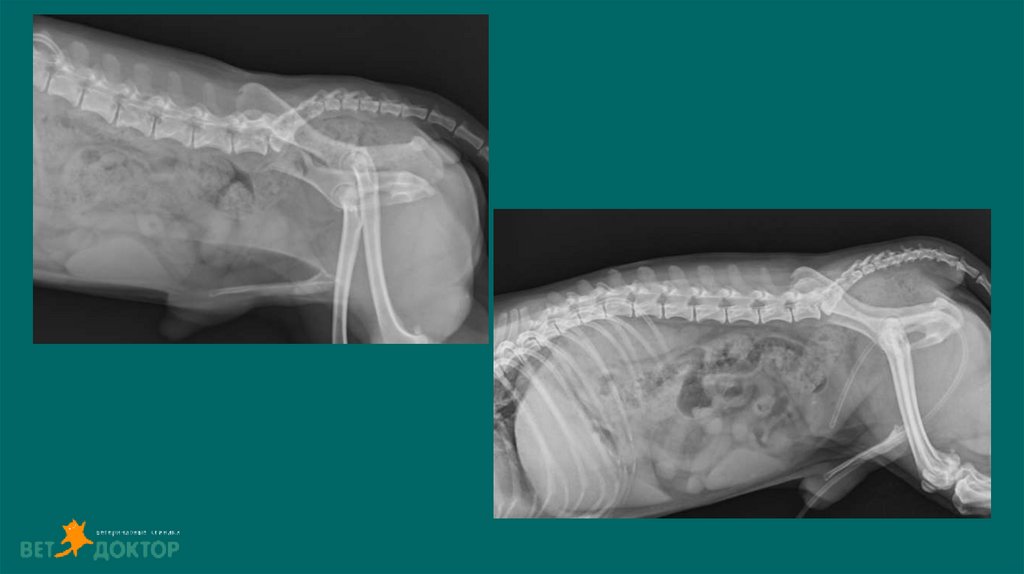

36. Уретеролитиаз-гидронефроз

До 98% уретеролитов у кошек и до 50% у собак состоят из оксалата кальция(Berent, 2011).

Клинические признаки:

Резкое ухудшение состояния(отказ от еды, рвота, депрессия),снижение тургора ,уремический

запах из ротовой полости, увеличение/болезненность почки.

Синдром большой и маленькой почки

Диагноз: УЗИ. Рентген. Пиелография. КТ(урография)

Доп.методы :ОАМ/СБК/Бак.посев мочи.

37. Обструкция мочеточника

Обструкция приводит к снижению почечного кровотока на 60-% в первые 24 часа и на 80% за

первые 2 недели.(Berent, 2011).

Если обструкция устранена в течении 4 дней, прогноз на восстановление функции почек

хороший. Через 14 дней СКФ восстановится примерно на 50% от первоначального уровня.

При обструкции более 40 дней возможно восстановление только небольшого числа нефронов

или функции почек может быть полностью утеряна( Kyles,2006).